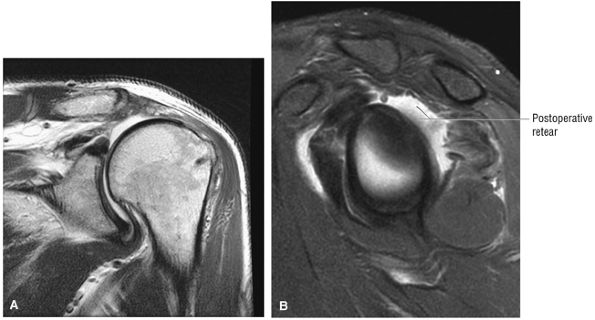

FIGURE 8.102 ● (A) The anterior undersurface of the acromion and the coracoacromial ligament form the coracoacromial arch. The subacromial subdeltoid bursa facilitates the passage of the rotator cuff and proximal humerus under the coracoacromial arch. (B) A superior axial image shows the anterior-to-posterior extent of the coracoacromial (CA) ligament perpendicular to the supraspinatus tendon. The fluid in the subacromial-subdeltoid bursa represents fluid between two serosal surfaces in contact with each other. One serosal surface is contributed by the undersurface of the coracoacromial arch and deltoid, and the other serosal surface is on the bursal side of the cuff.

|

![]() |